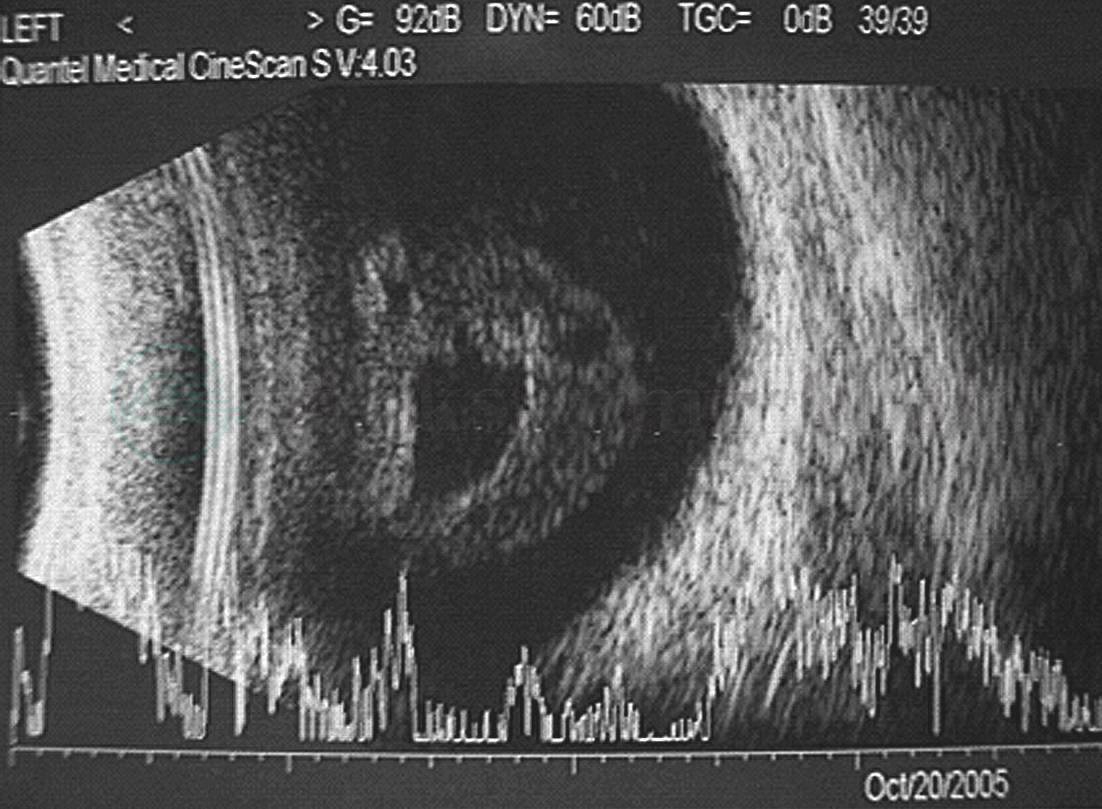

图3 真菌性眼内炎

B超示玻璃体腔较为致密的混浊和机化条索